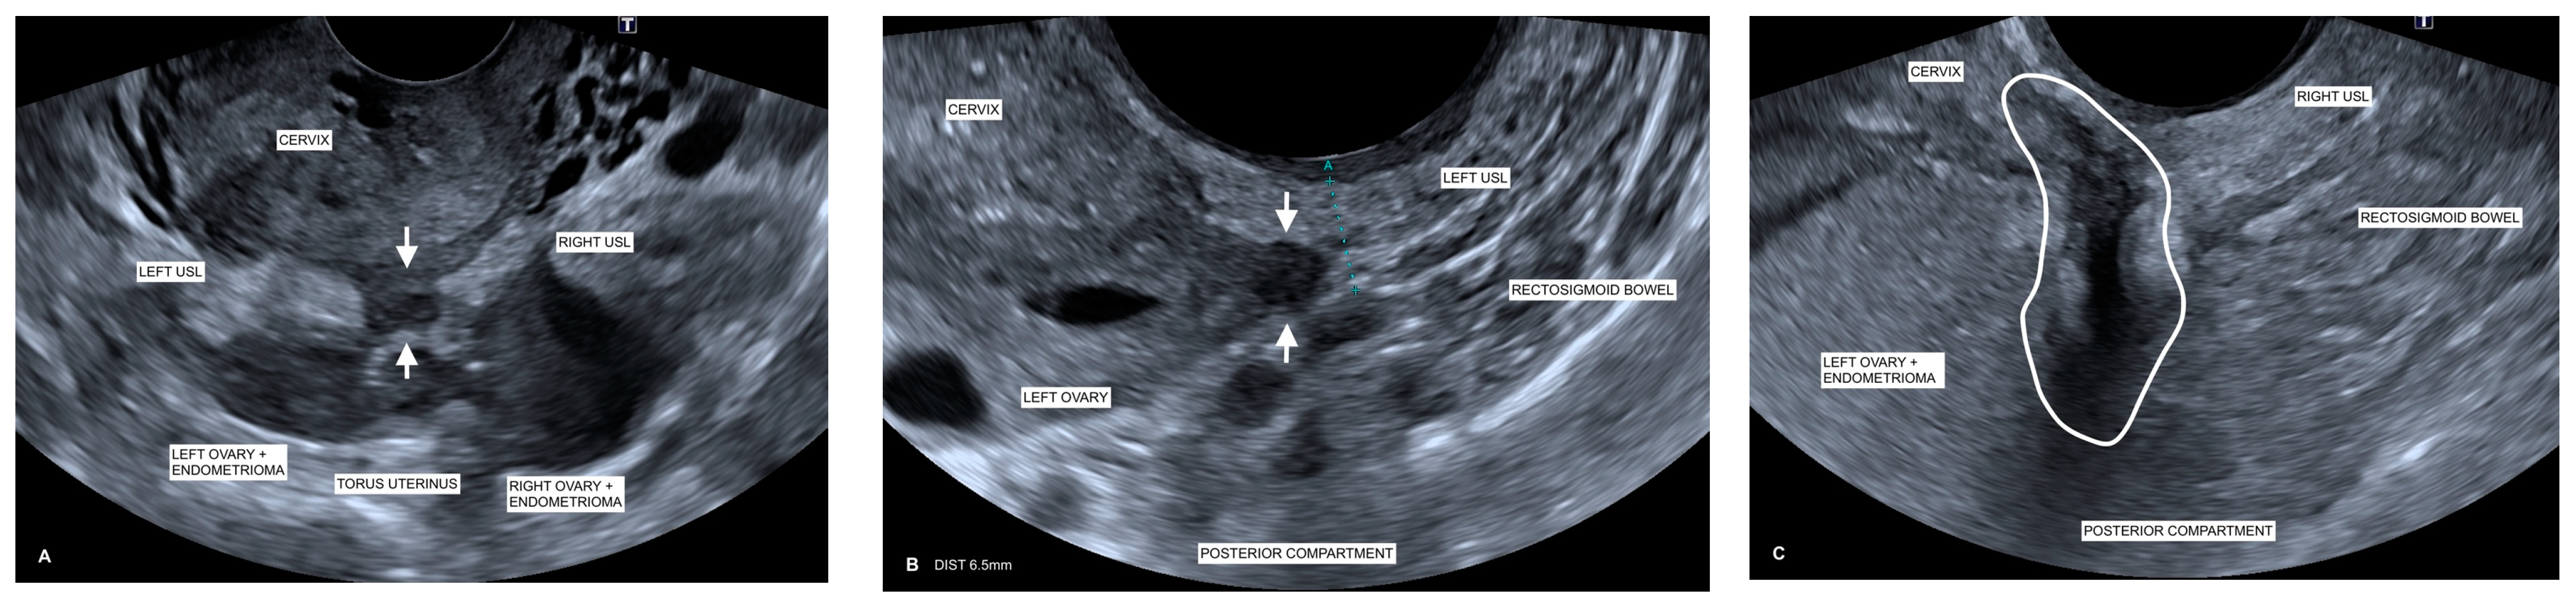

Clinically, during TVS, USLs would not be examined in isolation. However, USL examination in a routine pelvic scan is a useful starting point on its own diagnostic merit [9,12,14] to prompt further extension of the pelvic scan to look for other markers of endometriosis in the surrounding structures when a woman presents with pelvic pain [45]. Figure 4A illustrates the extensive nature of endometriosis demonstrating the association of the medialization of both ovaries with endometriomas adherent to the USLs as well as an endometriotic nodule at the TU. SST at this location was described as “sharp” with a total 13/15 pain score.

Figure 4.

Ultrasound images correlating patient TVS and SST. (A) Endometriomas/medialized ovaries to USLs: Transverse TVS image shows there are bilateral endometriomas and medialization of both ovaries adherent to the USLs (right and left as labeled) at the torus uterinus. A focal endometriotic nodule (arrows) can be seen between the right and left USLs. This patient has confirmed endometriosis associated with long-standing pelvic pain. Correlating SST at this location was described as “sharp” with a total 13/15 pain score. (B) Thickened USL and nodule: USL DE in a woman with severe pelvic pain and dyspareunia who was confirmed to have extensive endometriosis in laparoscopy. Sagittal TVS image shows an irregular and thickened left USL (labeled with caliper measuring 6.5 mm) with adherence of the left ovary (labeled). There is an associated focal endometriotic nodule (arrows) adherent to the adjacent structures. Calipers demonstrate a 6.5 mm thickness of the left USL measured at the thickest point. Correlating SST at this location was described as “sharp” with a total 12/15 pain score. (C) Rectosigmoid DE adherent to USL: Sagittal TVS image demonstrating extensive deep infiltrative endometriosis. Endometriosis plaque deposits (circled) can be seen at the level of the rectosigmoid bowel, tethered to the inferior margin of the left ovary (labeled). The left ovary is medialized, with an endometrioma adherent to the torus uterinus, extending to the right USL. Correlating SST at this location was described as “sharp” with a total 10/15 pain score.

It has been previously established that the presence of a rectovaginal endometriotic nodule is always associated with pelvic pain, dysmenorrhea, and/or deep dyspareunia [2,5,21,22]. This study supported these findings, with patients reporting a particularly high degree of SST pain scores (12.8 ± 0.38), with a range of 10–14 in the patients with focal DE nodules of the USL. Findings also showed that there was a strong positive correlation with the pain score where USL nodules were identified (r = 0.70), as well as with USL thickness (r = 0.74), since USL thickness can be an indicator of DE disease [12]. Figure 4B illustrates these findings, showing an irregular and thickened left USL with adherence of the left ovary associated with a focal endometriotic nodule, with the correlating SST at this location described as “sharp” with a total 12/15 pain score. An explanation for this is that the growth of nerve fibers in endometriotic deposits is considered a mechanism of severe pain in endometriosis [17,18,46] and that there is a close histological relationship between some deep retroperitoneal endometriotic lesions and the subperitoneal nerves and that this relationship is correlated with pain [17]. It has also been demonstrated that in rectovaginal septum endometriotic nodules, a high proportion of the nerves is encapsulated in the nodular fibrosis of the deposit [2]. Endometriotic lesions are also found in close histological relationship with the nerves of the colon, even at a distance from the palpated area, and seem to infiltrate the large bowel with tenderness around the nerves [17]. In essence, a characteristic of DE nodules is that they are “pain triggers” [44]. Figure 4C visualizes this with rectosigmoid bowel DE adherent to the inferior margin of the ovarian endometrioma, extending to the right USL. Correlating SST at this location was described as “sharp” with a total 10/15 pain score.